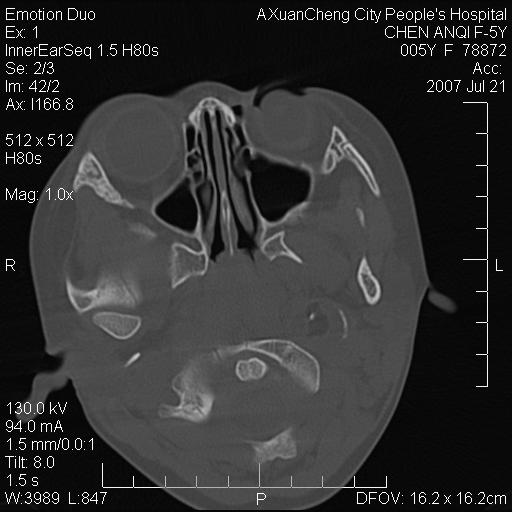

标题: PED0273:5岁,左耳流脓痛疼一周,颅底骨质破坏 [打印本页]

标题: PED0273:5岁,左耳流脓痛疼一周,颅底骨质破坏

患儿5岁,左耳流脓痛疼一周,左外耳道肉芽组织填塞 软组织窗显示病灶内结节状低密度影为气体密度

左侧中耳炎并胆脂瘤,左颞骨岩部骨质破坏并颅内感染积气。

补充:腺样体肥大.